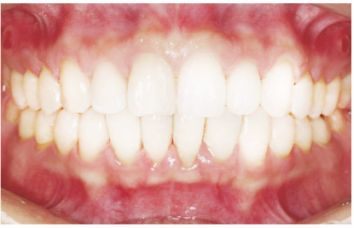

种植修复后照片

这一位老先生则选择了All-on-4种植技术,即拔即种,上下颌分别种植4个植体就完成了全口牙齿修复,费用降低了不少,而且创伤小,恢复快。